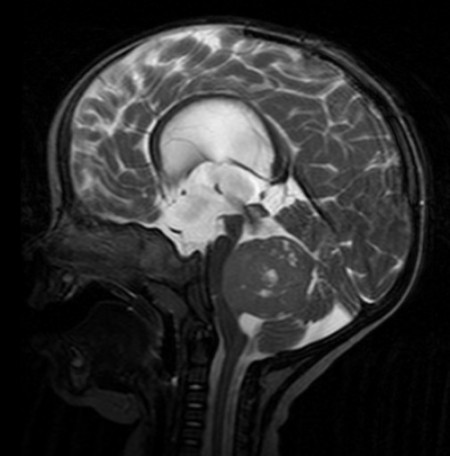

Pesquisadores da USP descobrem proteínas e microRNAS associados a tumor cerebral que acomete crianças e adolescentes e que normalmente é detectado em fase avançada; descoberta pode contribuir para o diagnóstico precoce e facilitar tratamento (meduloblastoma diagnosticado por ressonância magnética; imagem: Wikimedia Commons)